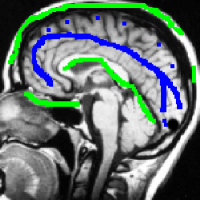

Finally, the “weighted cut” is recovered in (26), and the “smoothness term” is compatible with large variations of at the boundary of objects because of a large denominator () in the contour area. An illustration of optimal and on an image is shown on Fig. 2.

4.1 Metrication artifacts and minimal surfaces

We begin by comparing the CCMF segmentation result with the classical max-flow algorithm (graph cuts). Figure 3 shows the segmentation of a brain, in which the contours obtained by graph cuts are noticeably blocky in the areas of weak gradient, while the contours obtained by both AT-CMF and CCMF are smooth.

Figure 2 displays the performance results for these algorithms. The Dice coefficient is a similarity measure between sets (segmentation and ground truth), ranging from 0 to 1.0 for no match and a perfect match respectively. All the tested algorithms show very good results, with a Dice coefficient of 0.95–0.97 for the well positioned seeds, and 0.89–0.92 for the second set of seeds, further away from the objects. The CCMF and AT-CMF results are really close, and the mean is better than the GC and the CP-TV results.